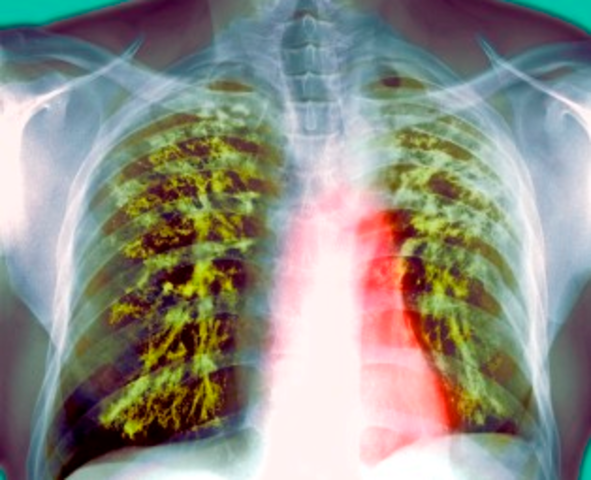

• Tuberculosis

Tuberculosis

Tuberculosis is an infectious bacterial disease characterized by the growth of nodules (tubercles) in the tissue. In the 18th and 19th centuries, tuberculosis severely rampaged throughout Europe and North America. In 1882 this problem was solved by the German microbiologist Robert Koch, who discovered the causes of tuberculosis. The symptoms are severe coughing (sometimes with mucus or blood), nasty chills, fatigue , fever, loss of weight, loss of appetite, and night sweats.